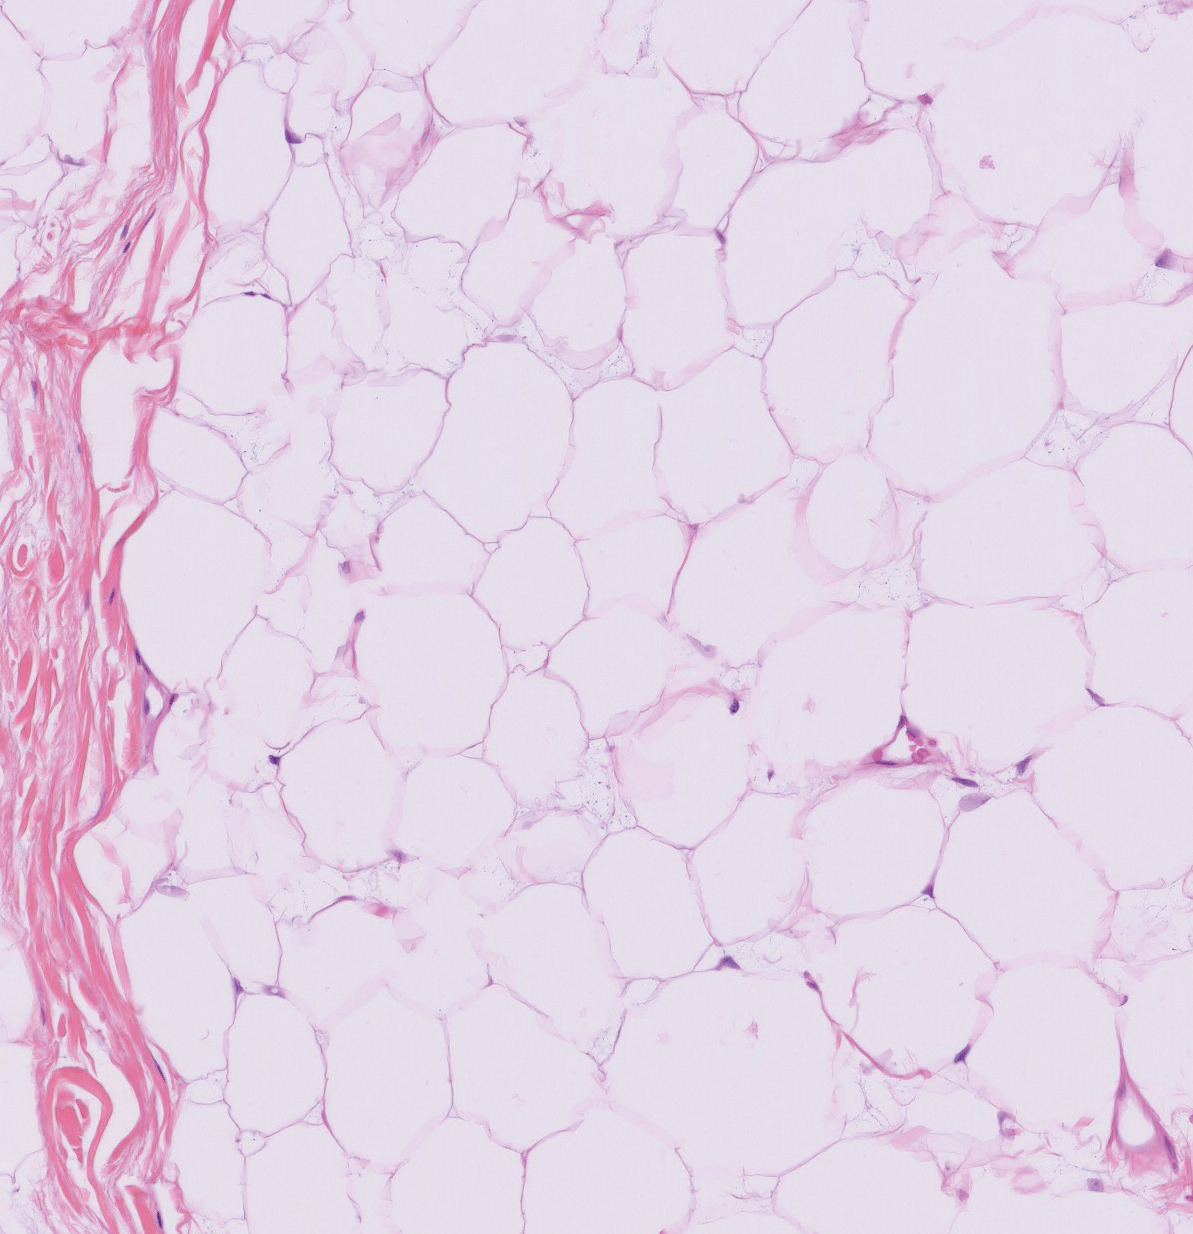

L’examen clinique révèle une tuméfaction sous-cutanée de la marge anale (fig. 1).